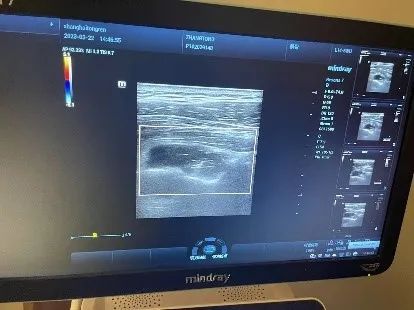

考虑到囊肿位置特殊性,且存在压迫神经,经过与患者本人沟通,行超声引导下局部囊肿穿刺抽液。

共抽出5ml血液、胶冻状、泡沫状囊肿液体。后于肩胛上神经周围予以局部注射得宝松、利多卡因起到局部消炎作用。